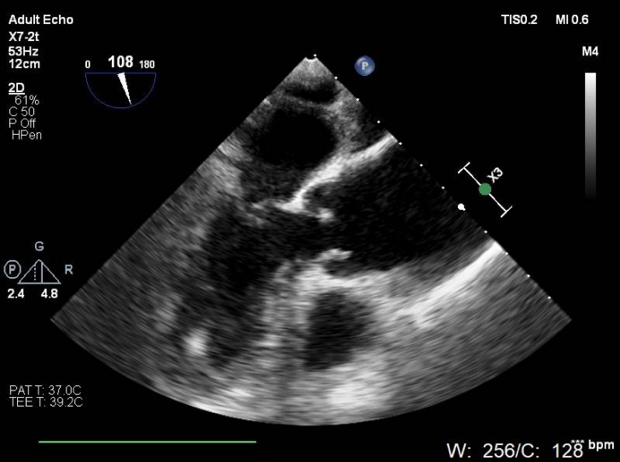

心脏超声

LVEF 35 %,主动脉瓣钙化,主动脉瓣三叶瓣,开放受限,闭合不拢,主动脉瓣峰值流速4.3m/s,峰值压差73mmHg,平均压差37mmHg,三尖瓣重度反流,TAPSE 13mm。

食道超声释放前

食道超声释放后

瓣膜释放后,食道超声及造影均提示瓣膜无残余反流。